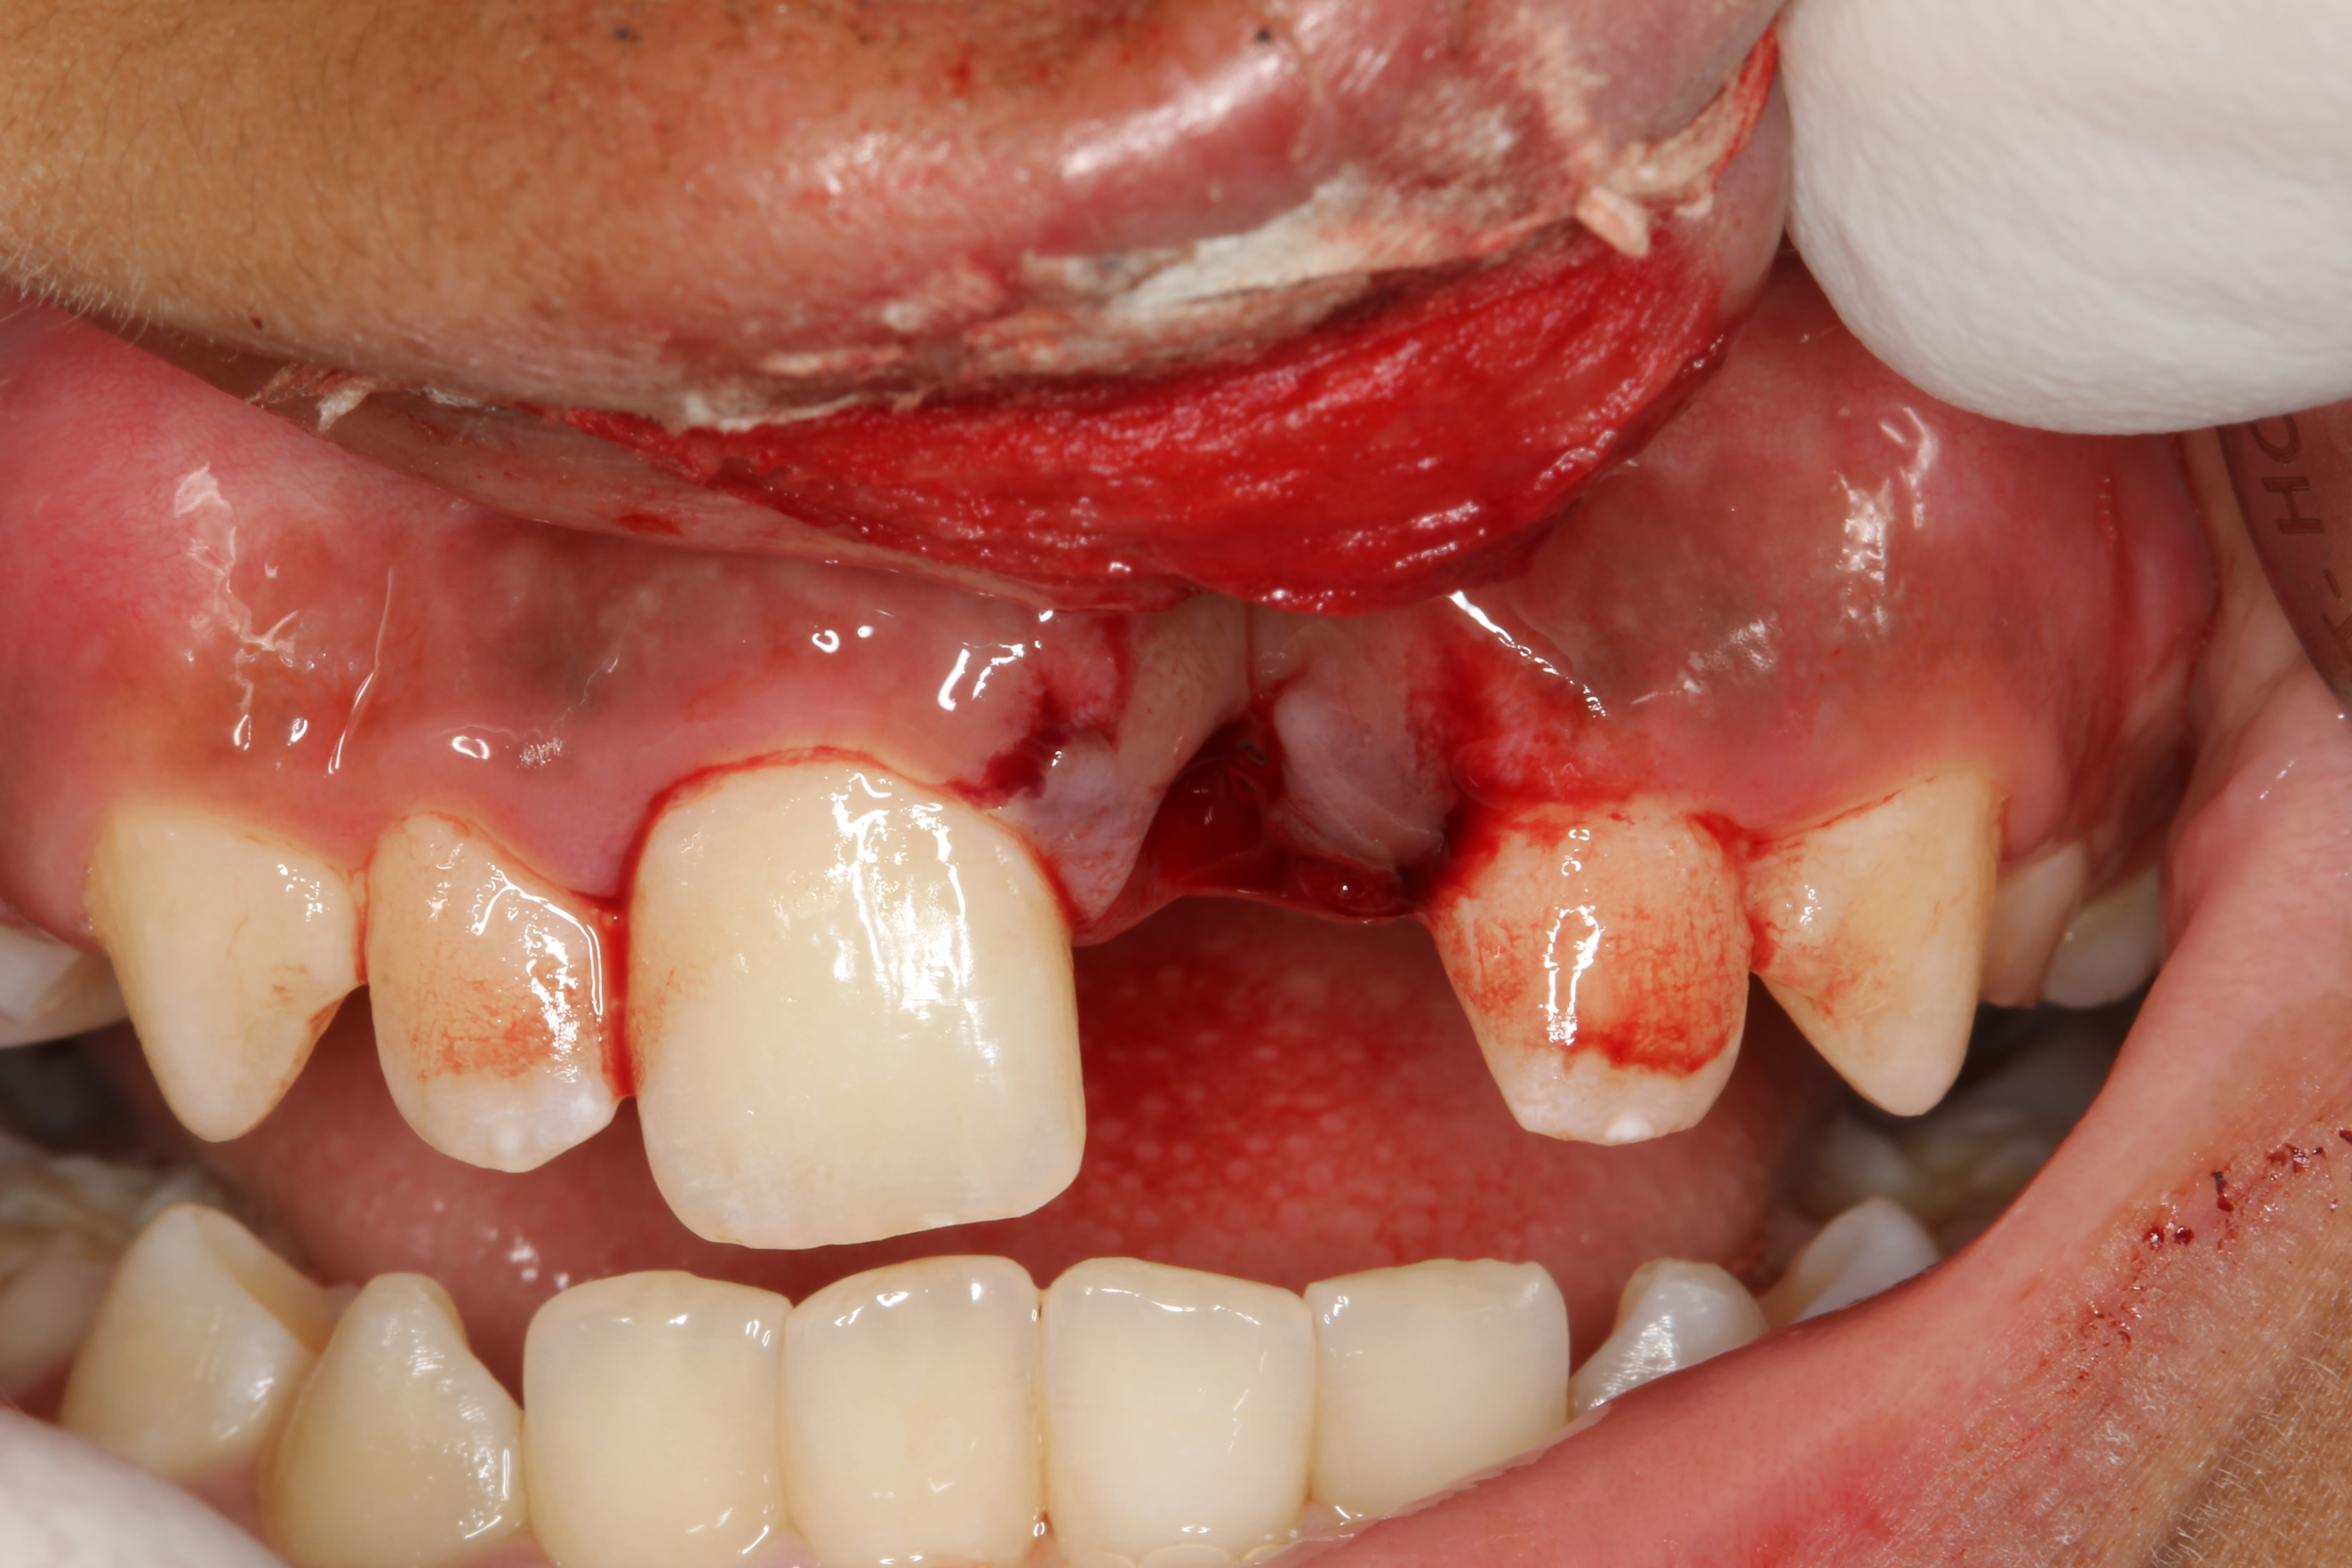

Petit cas clinique d'un traumatisme avec expulsion de 21 sur un enfant de 11 ans et 10 mois.

- 12/22 concussion - 11 subluxation - 21 expulsion

- lacération de la lèvre supérieure

- rinçage actif de la dent et de l'alvéole avec sérum physiologique, dent laissée dans le sérum physiologique le temps de faire anesthésie, radio, photos, etc...

- anesthésie locale

- radiographie apicale + OPT

- repositionnement de la dent dans l'alvéole

- contention souple de 13 à 23

- suture de la lèvre

- prescription amoxicilline / anti-inflammatoires / bain de bouche